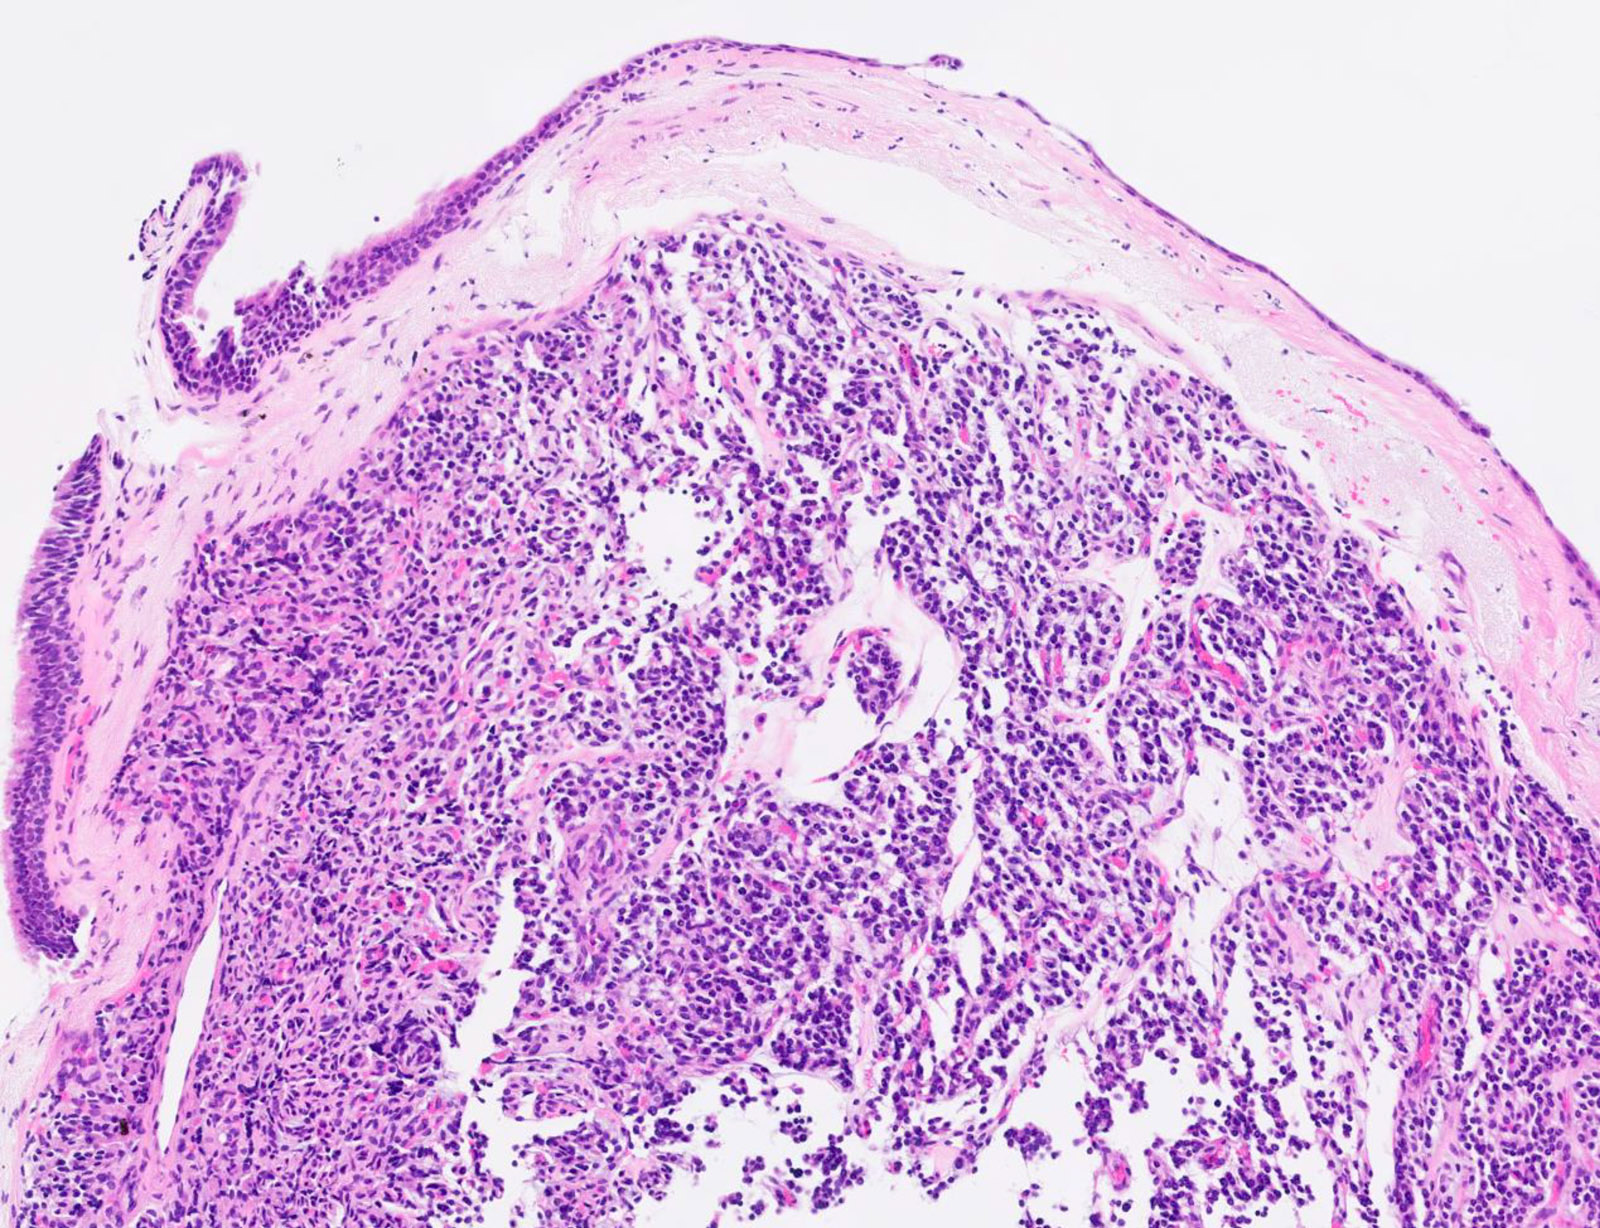

Microscopic (histologic) description

- Diagnostic criteria

- Neuroendocrine tumor with size ≥ 5 mm with < 2 mitoses/2 mm2 and absence of necrosis

- Neuroendocrine growth pattern (organoid, trabecular, rosette formation, nested) or pseudoglandular, follicular and papillary growth

- Tumor cells are uniform with a polygonal shape, round to oval nuclei with salt and pepper chromatin as well as inconspicuous nucleoli and moderate to abundant eosinophilic cytoplasm

- Spindle cells and clear cell features can be seen

- Stroma is fine and highly vascularized; hyalinization, cartilage or bone formation are possible

- Reference: Curr Oncol 2018;25:S86

Microscopic (histologic) images

Contributed by Philippe Joubert, M.D., Ph.D., Jijgee Munkhdelger, M.D., Ph.D. and Andrey Bychkov, M.D., Ph.D.

A 55 year old woman had a lower left lobectomy showing a well circumscribed flesh colored tumor. Histologic details are shown in the image above. Regarding this entity, which of the following statements is true?

Practice answer #1

A. CDX2 is usually negative in the lung and is useful to differentiate from a metastasis of an intestinal origin. The image shows a tumor with a trabecular pattern and pseudorosettes. The stroma is highly vascularized. Tumor cells are monotonous with scant to moderate eosinophilic cytoplasm. Nuclei are round to oval with salt and pepper chromatin and inconspicuous nucleoli. No mitoses are seen. These features are consistent with a typical carcinoid lung tumor.